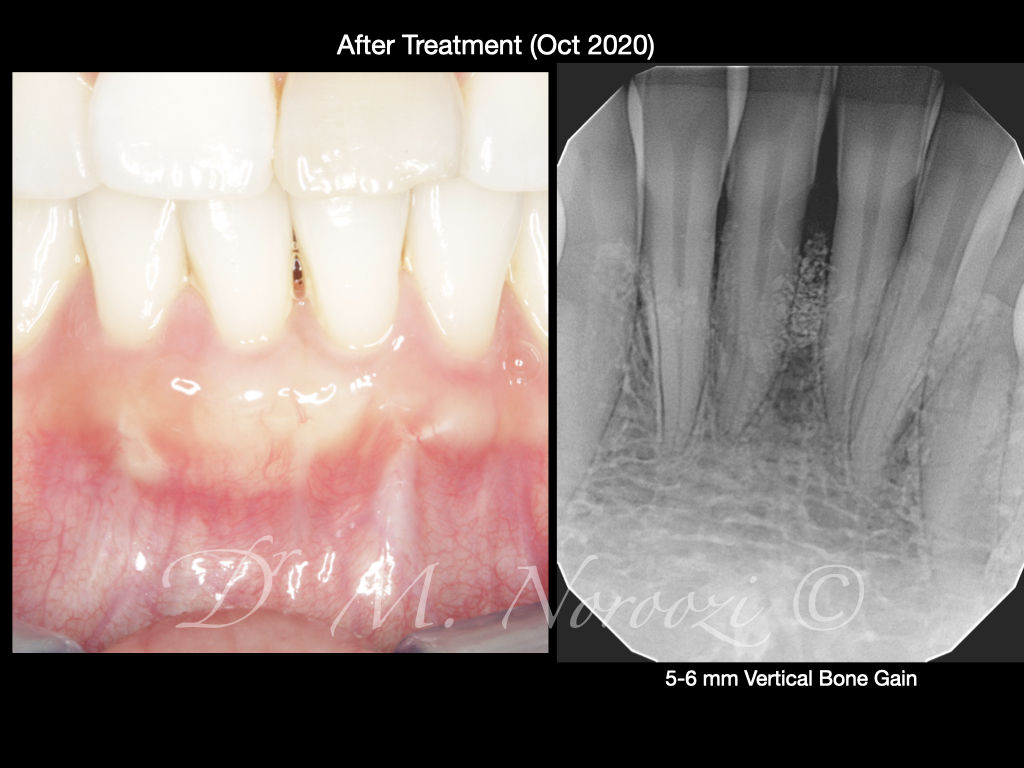

Guided Tissue Regeneration with Bone Graft & Growth Factors to Save teeth